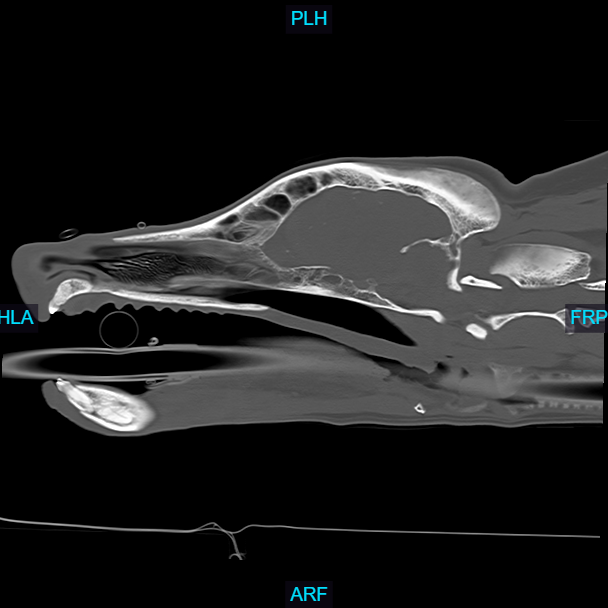

Computed Tomography (CT), also known as a CAT scan, is an advanced imaging technique that combines X-ray technology with computer processing to generate detailed cross-sectional images of an animal's internal structures.

The animal is typically sedated or anesthetized to remain still during the procedure, ensuring high-quality images. Special positioning aids may be used to maintain the correct posture. The animal is placed on a motorized table that moves through a circular opening of the CT scanner. The scanner consists of an X-ray tube that rotates around the animal, emitting X-rays from different angles. Veterinarians and veterinary radiologists analyze the CT images to identify abnormalities such as tumors, fractures, organ diseases, and other conditions. The high-resolution images allow for a detailed examination that is often not possible with traditional X-rays.

- Evaluating complex fractures, joint abnormalities, and spinal disorders.